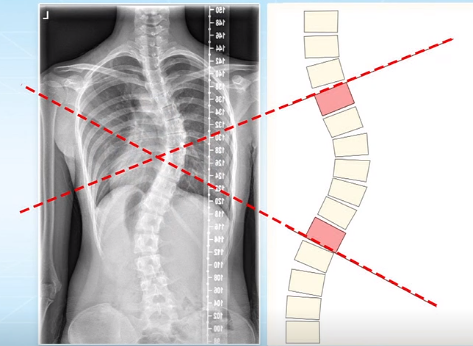

脊柱側(cè)彎的角度測(cè)量

脊柱側(cè)彎的角度測(cè)量 脊柱側(cè)彎的角度測(cè)量 脊柱側(cè)彎的角度測(cè)量...